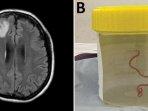

Kemungkinan besar cacing itu masuk dari kotoran ular yang menempel pada sayuran hijau yang dimakan oleh perempuan tersebut.